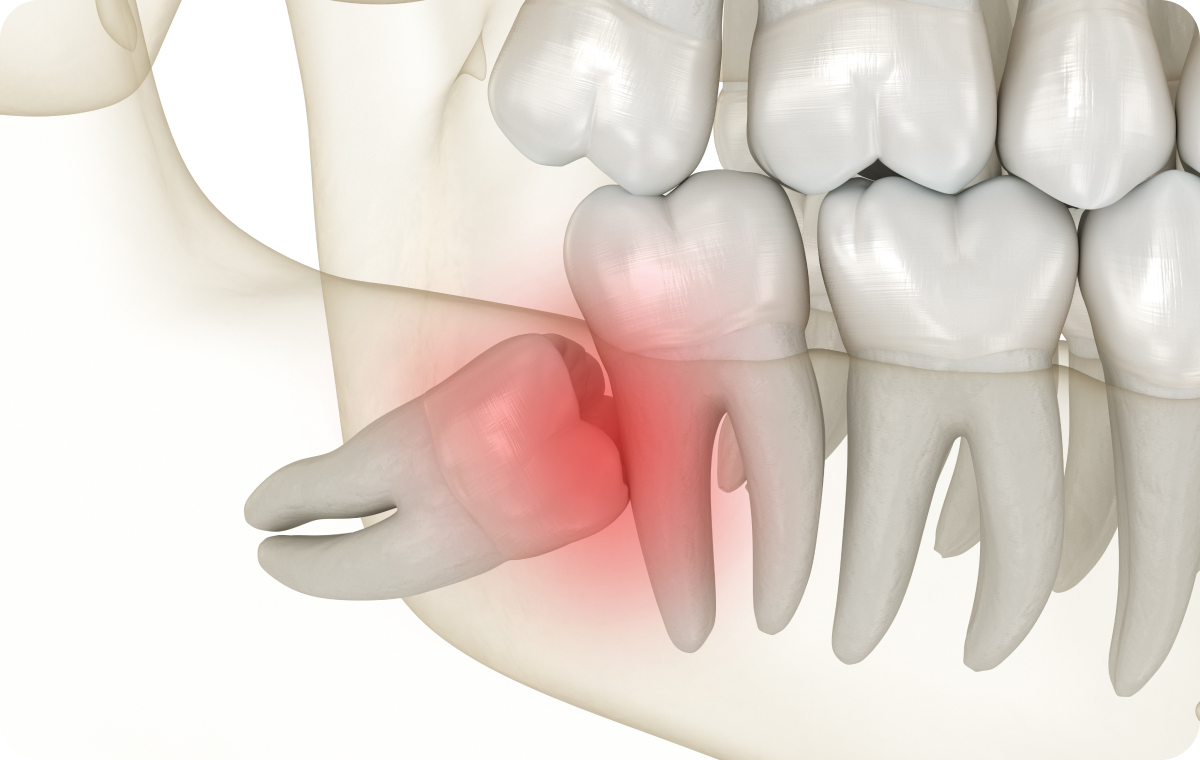

Chez de nombreux patients, les mâchoires ne disposent pas d’un espace suffisant pour accueillir correctement les dents de sagesse. Cette situation peut entraîner une éruption partielle ou une position anormale de la dent.

Lorsque la dent ne sort pas complètement, une partie reste sous la gencive, favorisant l’accumulation de bactéries et de débris alimentaires.

À long terme, ce contexte peut provoquer des inflammations locales, des douleurs répétées ou des difficultés de nettoyage. L’extraction des dents de sagesse est alors envisagée afin de limiter ces désagréments et d’éviter l’apparition de complications.

Une dent de sagesse partiellement sortie peut être à l’origine d’une inflammation de la gencive environnante, appelée péricoronarite. Cette affection se manifeste souvent par une douleur, un gonflement, voire une difficulté à ouvrir la bouche. Dans certains cas, une fièvre ou une gêne à la mastication peuvent également apparaître.

Impact sur les dents voisines

Une dent de sagesse mal positionnée peut exercer une pression sur la molaire adjacente. Cette situation favorise parfois l’apparition de caries sur la dent voisine, en raison d’un accès difficile au brossage. De plus, des résorptions osseuses ou dentaires peuvent survenir dans certains cas.